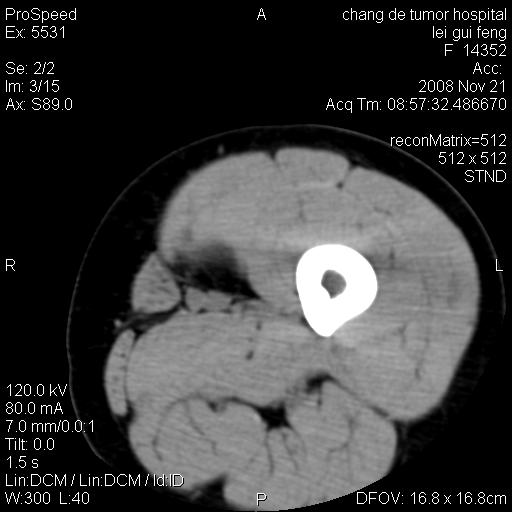

标题: CT16807:女 41 无不适 [打印本页]

标题: CT16807:女 41 无不适

双是软组织肿瘤,病灶内多发钙化,另可见多量脂肪密度影,考虑畸胎瘤,血管瘤,不除外其他